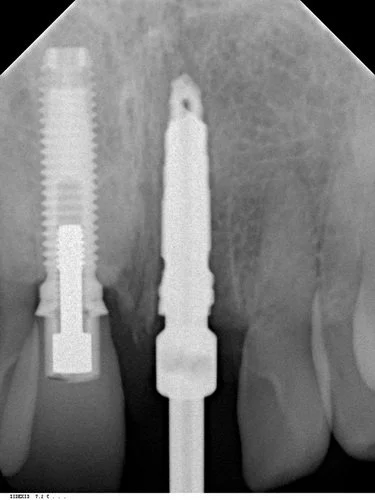

Tooth 21 was removed and due to excellent primary stability being achievable, with good interproximal bone height (Tarnow 1998) a Replace Select implant was placed immediately, with 40+ Ncm of torque being achieved. This allowed for placement of an immediate provisional restoration. The patient’s natural crown was used along with a titanium provisional abutment to construct a pleasing provisional restoration.

The abutment screw was torqued finger tight (~15 Ncm). The access cavity was then restored with cotton pellet and Cavit. The occlusion was adjusted to give no shim stock hold in ICP and no guidance in protrusion or lateral excursion.